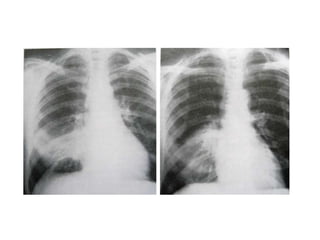

Chest radiograph shows silhouette sign, with

obscuration of right border of heart (arrows).

Lingular segment consolidation

Chest radiograph showssilhouette sign, with obscuration of right border of heart (arrows).